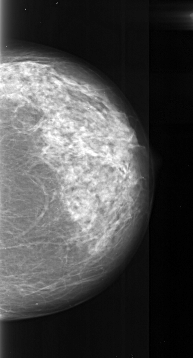

A_1023_1.LEFT_CC

LEFT_CC LINES 4786 PIXELS_PER_LINE 2176 BITS_PER_PIXEL 16 RESOLUTION 42 NON_OVERLAY